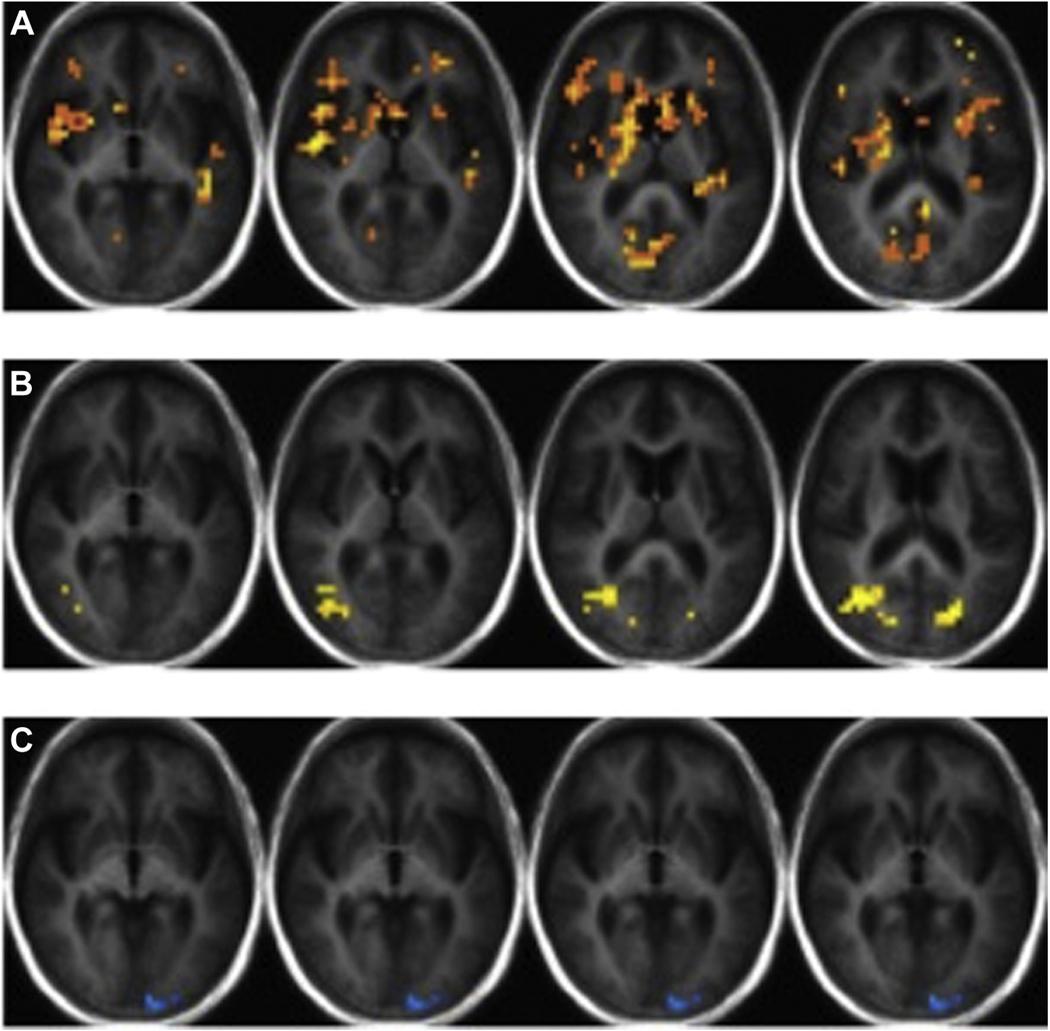

The current study sought to examine the interaction of sex and Apolipoprotein ε status on olfactory recognition memory within non-demented, older individuals. We separated 39 participants into groups based on ε status and sex. Each participant completed an olfactory memory recognition task during 2 functional magnetic resonance imaging scans and 1 structural scan. The ε carriers had greater functional recruitment of memory regions during false positives relative to ε non-carriers. During hits, the male ε carriers showed greater functional recruitment compared to female ε carriers. The ε carriers had larger bilateral putamen volumes relative to ε non-carriers. Neuroimaging data were significantly associated with Dementia Rating Scale scores solely in males. Results suggest differential olfactory memory processing in relation to sex and ε status. Male ε carriers in particular, demonstrated hyperactivation during recognition memory, which we suspect reflects neuronal compensation to maintain functional performance. Future studies should consider examining underlying mechanisms that contribute to these sex differences within ε carriers.

本研究旨在探究非痴呆老年个体中性别和载脂蛋白 E 状态对嗅觉识别记忆的交互作用。我们根据 ε 状态和性别将 39 名参与者分为两组。每位参与者在 2 次功能磁共振成像扫描和 1 次结构扫描期间完成嗅觉记忆识别任务。ε 携带者在假阳性时相对于 ε 非携带者有更大的记忆区域功能募集。在命中时,男性 ε 携带者的功能募集比女性 ε 携带者更大。ε 携带者的双侧壳核体积大于 ε 非携带者。神经影像学数据仅与男性的痴呆评定量表评分显著相关。结果表明,嗅觉记忆处理与性别和 ε 状态有关。特别是男性 ε 携带者在识别记忆过程中表现出过度激活,我们怀疑这反映了神经元的代偿作用,以维持功能表现。未来的研究应该考虑检查导致 ε 携带者中这些性别差异的潜在机制。